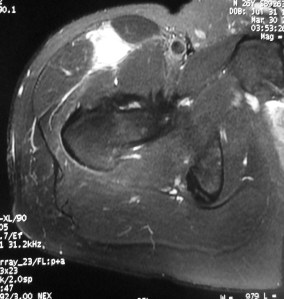

The Sports Physician referred him for an MRI scan.

The MRI scan showed a rupture of the proximal rectus femoris musculotendinous junction.

A bedside ultrasound scan in my clinic reviewed a completely torn rectus femoris and the torn end was still in the proximal third of his right thigh: